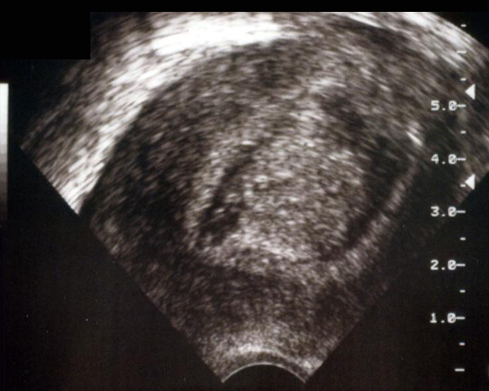

Hystérosonographie. Caillot flottant dans la cavité